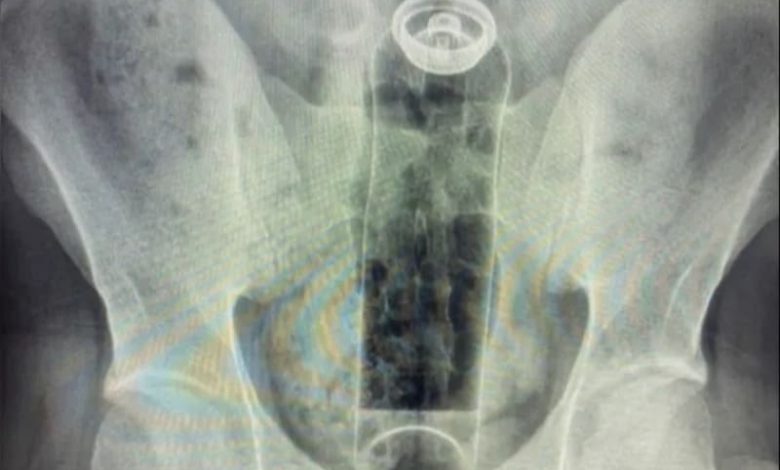

Um jovem de 19 anos, que não teve o nome divulgado, precisou de atendimento médico de urgência depois que um frasco de desodorante ficou preso em seu ânus, na cidade de São Paulo.

Segundo Brosco, o paciente relatou que o acidente aconteceu durante uma “brincadeira” sexual. O frasco subiu para dentro do reto e, apesar de várias tentativas de remoção em casa, foi necessário buscar ajuda profissional.

O médico explicou ainda que os movimentos naturais do intestino e o vácuo criado na região dificultam a retirada manual de objetos estranhos.